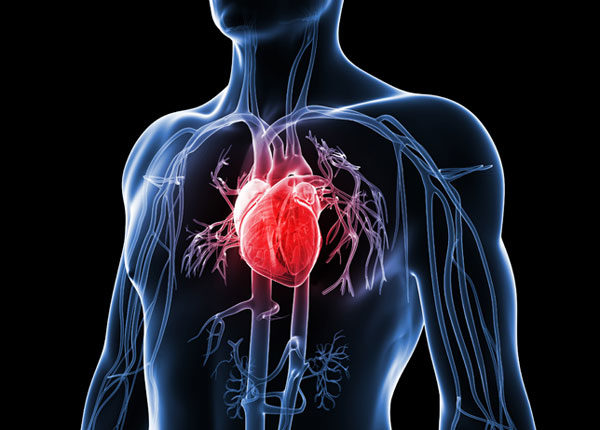

Tips jantung sihat perlu diketahuai oleh semua orang kerana Jantung merupakan organ penting bagi manusia. Ia berfungsi untuk mengepam dan mengedarkan darah ke seluruh badan. Jantung merupakan salah satu organ yang sangat penting dan perlu dijaga dengan baik.

Penyakit jantung boleh menyerang sesiapa sahaja tanpa mengira jantina mahupun umur. Oleh itu anda perlu lebih mementingkan penjagaan kesihatan jantung, agar anda akan hidup lebih sihat dan lebih panjang usia. Diharapkan tips jantung sihat yang akan dikongsikan ini akan memberi manfaat kepada pembaca.